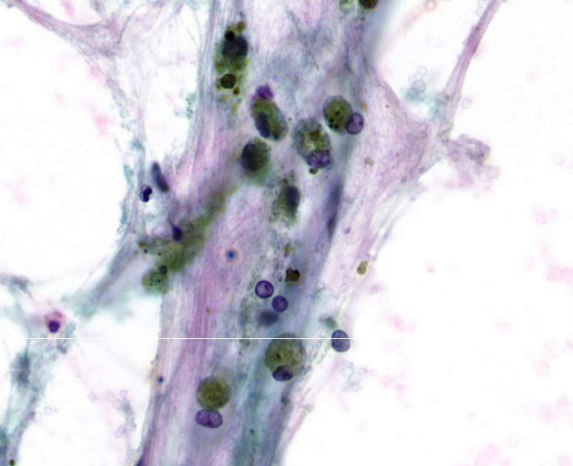

alveolar macrophages

squamous metaplasia